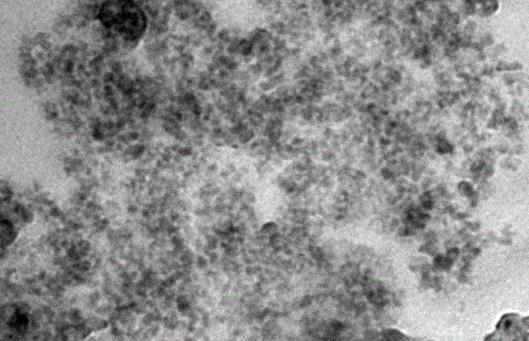

目的为满足颌面部骨缺损修复的需?文中旨在构建氧化石墨?GO)修饰的三维联通纳米氧化锆(ZrO2)骨组织工程支?并评价GO修饰后复合支架的表面形貌、机械强度以及细胞相容性。方法采用改良Hummers法制备GO,扫描电镜、透射电镜及傅里叶红外光谱进行表征。硅烷介导下,将ZrO2支架与不同浓?0.5??.5mg/mL)GO分散液结?选择表面均匀结合GO的复合支架进行压缩强度测?并与人牙髓干细胞(hDPSCs)共培?肌动蛋白染色观察细胞在支架上生长情况,MTS法检测细胞活力。结果表征结果显礹扫描电镜下观?GO呈片?可见褶皱的表面形?部分GO片层在边缘折叠翘赶透射电镜下可清晰地观察到GO呈轻纱状半透明微皱的片状结?高分辨过滤像中可见该区域的晶体结构显示出与石墨一样的六元环结构。高倍电镜下1.0mg/mLGO-ZrO2支架可见到薄层的GO沉积在支架骨架的裂纹?连接裂纹两端,并且可观察到陶瓷颗粒表面沉积带有褶皱的层状GO。机械性能对比结果显示,GO-ZrO2支架的压缩强度为([1.292±0.087)Mpa]较ZrO2支架([1.031±0.076)Mpa]显著增加(P<0.05)。与单纯ZrO2支架相比,在GO-ZrO2支架上均可见细胞更为密集的伸展黏附于支架表面,表现出更为活跃的细胞增殖状态。细胞活力检测结果显?hDPSCs在GO-ZrO2支架上培???d?细胞活力均显著高于单纯ZrO2支架(P<0.05)。结论GO修饰ZrO2支架可改善机械性能,促进hDPSCs的早期增?呈现出良好的细胞相容性?..